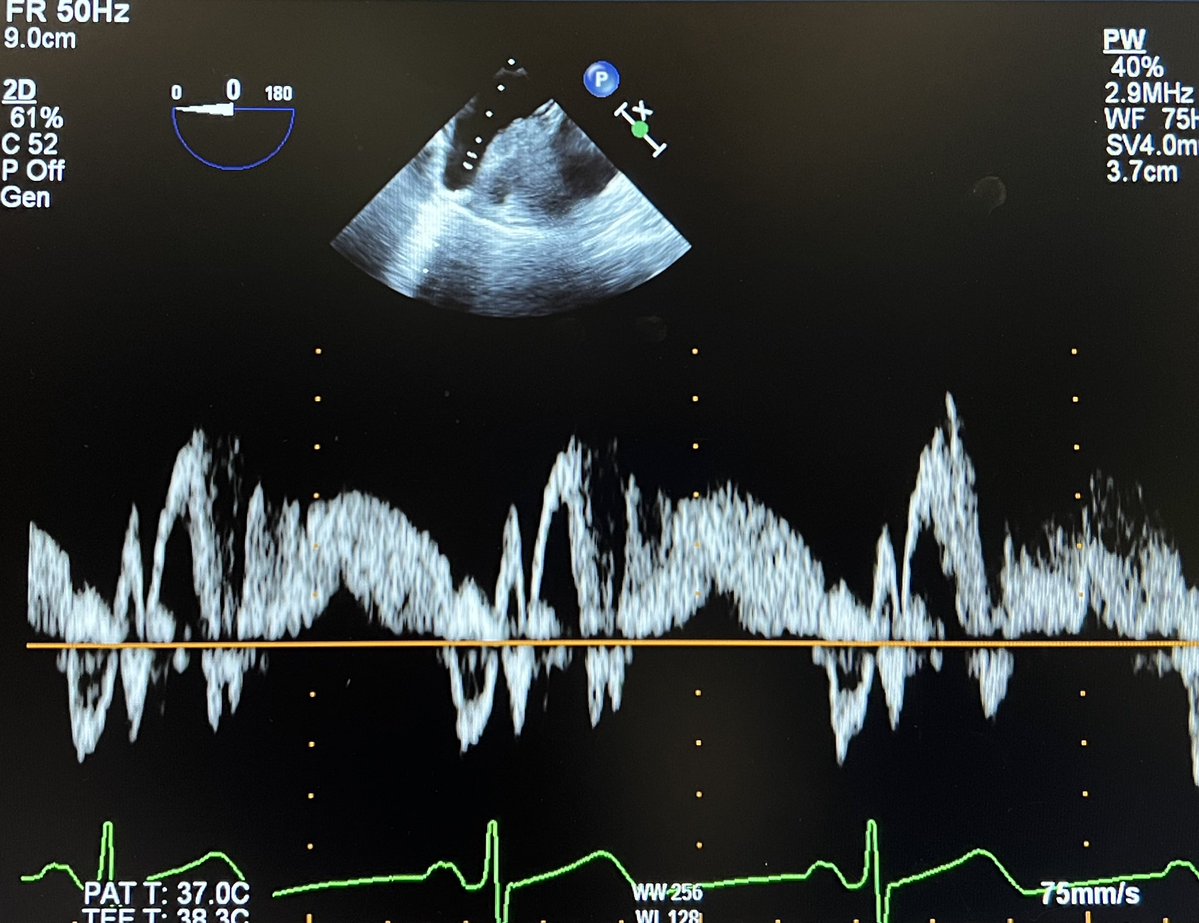

#echofirst ✅ Simple Doppler quiz for trainees ✅ Identify the waves on this tracing & the diagnosis @BryanTanMD @Hragy @JaeKOh2 @EchoSoliman @argulian @iamritu @bwoody58 @PWesslyMD @PWengrofskyMD @DavidWienerMD @JohnHenryDean

#echofirst ✅ Time to close out. See answer below. ✅ Pink: S1 (due to atrial relaxation), Blue: S2 (systolic), Orange: diastolic, Yellow: atrial reversal ✅ Prominent Ar, slow diastolic velocity decline & systolic predominance indicate DD & ⬆️ LVEFP ✅ Most got it right! 🙏